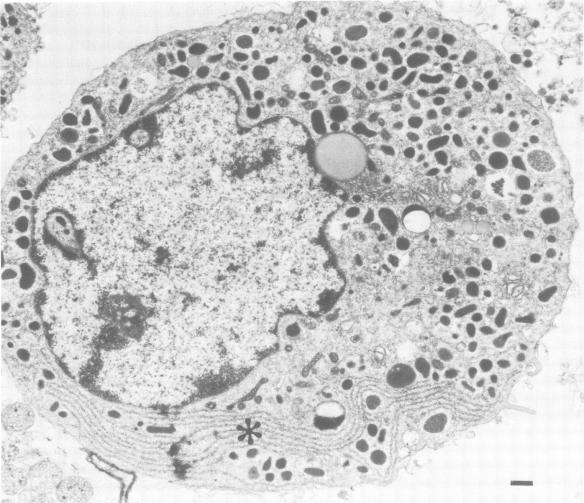

Temporal and spatial changes in the concentration of cytosolic free calcium ([Ca2+]i) in response to a variety of secretagogues have been examined in adrenal chromaffin cells using digital video imaging of fura-2-loaded cells. Depolarization of the cells with high K+ or challenge with nicotine resulted in a rapid and transient elevation of [Ca2+]i beneath the plasma membrane consistent with Ca2+ entry through channels. This was followed by a late phase in which [Ca2+]i rose within the cell interior. Agonists that act through mobilization of inositol phosphates produced an elevation in [Ca2+]i that was most marked in an internal region of the cell presumed to be the site of IP3-sensitive stores. When the same cells were challenged with nicotine or high K+, to trigger Ca2+ entry through voltage-dependent channels, the rise in [Ca2+]i was most prominent in the same localized region of the cells. These results suggest that Ca2+ entry through voltage-dependent channels results in release of Ca2+ from internal stores and that the bulk of the measured rise in [Ca2+]i is not close to the exocytotic sites on the plasma membrane. Analysis of the time courses of changes in [Ca2+]i in response to bradykinin, angiotensin II and muscarinic agonists showed that these agonists produced highly heterogeneous responses in the cell population. This heterogeneity was most marked with muscarinic agonists which in some cells elicited oscillatory changes in [Ca2+]i. Such heterogeneous changes in [Ca2+]i were relatively ineffective in eliciting catecholamine secretion from chromaffin cells. A single large Ca2+ transient, with a component of the rise in [Ca2+]i occurring beneath the plasma membrane, may be the most potent signal for secretion.

利用fura - 2负载细胞的数字视频成像技术,研究了肾上腺嗜铬细胞中胞质游离钙浓度([Ca2+]i)在响应多种促分泌剂时的时空变化。用高钾使细胞去极化或用尼古丁刺激,导致质膜下[Ca2+]i迅速短暂升高,这与通过通道的Ca2+内流一致。随后是一个后期阶段,其中[Ca2+]i在细胞内部升高。通过动员肌醇磷酸起作用的激动剂使[Ca2+]i升高,在细胞内部一个被认为是IP3敏感储存部位的区域最为明显。当用尼古丁或高钾刺激相同的细胞,以触发通过电压依赖性通道的Ca2+内流时,[Ca2+]i的升高在细胞的同一局部区域最为显著。这些结果表明,通过电压依赖性通道的Ca2+内流导致Ca2+从内部储存释放,并且所测量的[Ca2+]i升高的大部分并不靠近质膜上的胞吐部位。对缓激肽、血管紧张素II和毒蕈碱激动剂响应时[Ca2+]i变化的时间进程分析表明,这些激动剂在细胞群体中产生高度异质性的反应。这种异质性在毒蕈碱激动剂中最为明显,在某些细胞中它会引起[Ca2+]i的振荡变化。[Ca2+]i的这种异质性变化在引发嗜铬细胞分泌儿茶酚胺方面相对无效。单个大的Ca2+瞬变,其中[Ca2+]i升高的一部分发生在质膜下,可能是最有效的分泌信号。